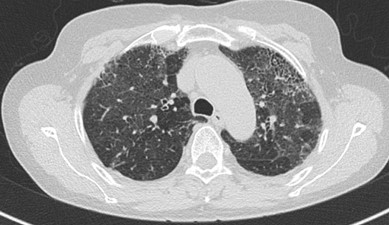

病例1:患者,男,60歲,因“咳嗽、活動(dòng)后氣促7個(gè)月”于2024年7月25日求診我院?;颊咴?個(gè)月內(nèi)先后4次就診其他醫(yī)院住院治療,均被診斷為“肺炎”,但治療后癥狀沒有改善,氣促反而加重。轉(zhuǎn)診我院后,間質(zhì)肺規(guī)范化診療中心主任張宏英經(jīng)詢問病史,患者從事木頭加工,考慮電鋸木粉吸入導(dǎo)致過敏性肺炎,經(jīng)影像科、病理科等多學(xué)科協(xié)助,最終確定了診斷:木屑所致的非纖維化型過敏性肺炎,治療不到1周,恢復(fù)出院。

病例5:患者,男,58歲,因“體檢發(fā)現(xiàn)肺部陰影20天”于2024年6月26日求診我院。既往接觸木屑、油漆,每1-2個(gè)月染頭發(fā)1次。

過敏原無處不在,但又很隱匿,宿主的易感性也不一樣。過敏性肺炎早發(fā)現(xiàn)、脫離環(huán)境就可以治愈,但是由于患者經(jīng)常未及時(shí)發(fā)現(xiàn)過敏原,對(duì)于早期肺部比較典型的影像特征也缺乏足夠的敏感性,仍繼續(xù)暴露在過敏環(huán)境中,最后發(fā)展成纖維化型過敏性肺炎。我院間質(zhì)肺規(guī)范化診療中心將盡可能詳盡地采集病史以發(fā)現(xiàn)可能存在的環(huán)境暴露因素以及時(shí)間軸關(guān)系,發(fā)揮多學(xué)科診療優(yōu)勢(shì),早發(fā)現(xiàn)早診斷,助力患者盡快脫離過敏原,避免不可逆的肺纖維化。